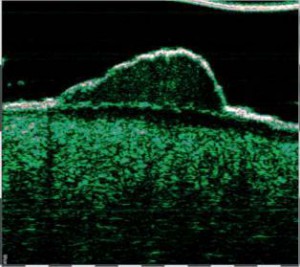

-Υπέρηχος Υψηλής Συχνότητας (HFUS) και Ιστολογία

-Διαφοροποίηση μεταξύ υπερτροφικών και χηλοειδών ουλών

-Διάγνωση μορφών ακμής